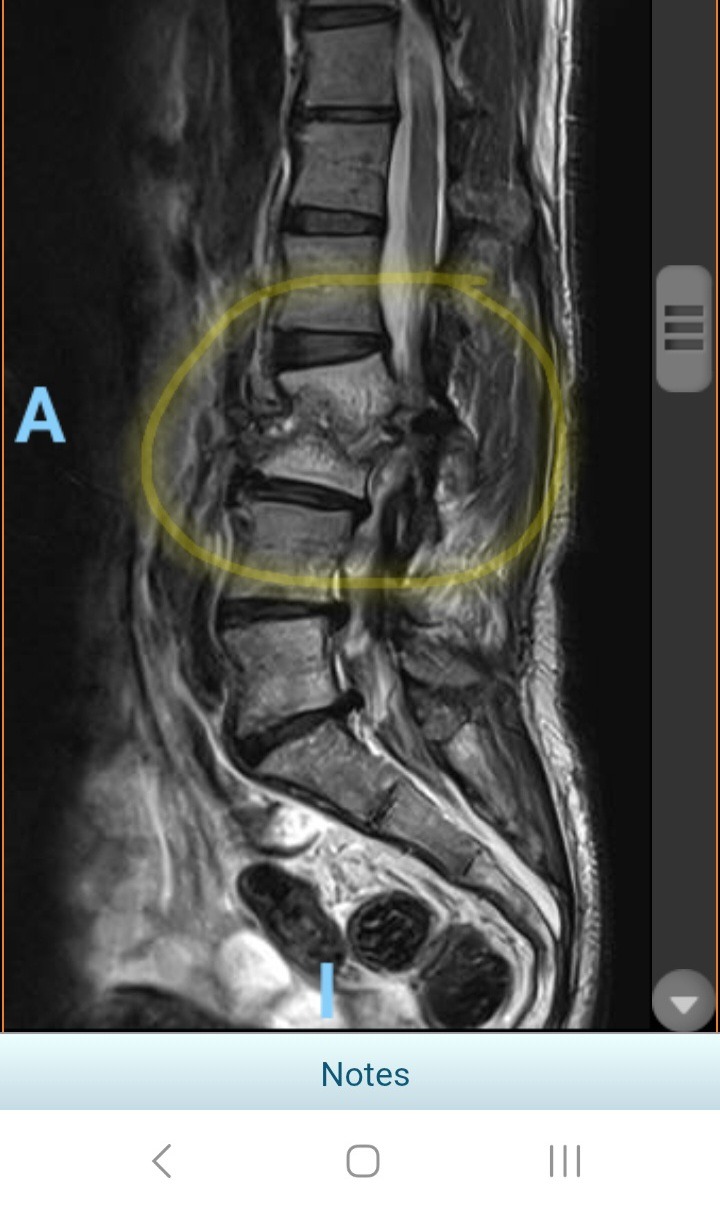

This went on for two months until I begged my chiropractor to look at me. He saw the swelling on my back and the pain I was in and told me he was recommending I go to the emergency room. The doctor ordered a CT scan to check on all my insides and discovered that I had what seemed to be an abscess on my spine. I was sent to the University of Iowa hospital where I was told how lucky I was that it hadn't gone septic, and was inpatient for almost two weeks. During that time, there was a lot of blood work and testing and finally a spinal biopsy of the infection and the affected bone. It was found to be an infection which requires IV antibiotics daily for at least six weeks, so I had a PICC line placed in my arm and had those arranged. I'll still be heading back and forth to the university a few times in the next few weeks in order to evaluate my progress. I am so thankful to be back at home now, with some answers, and with a bit of a plan.